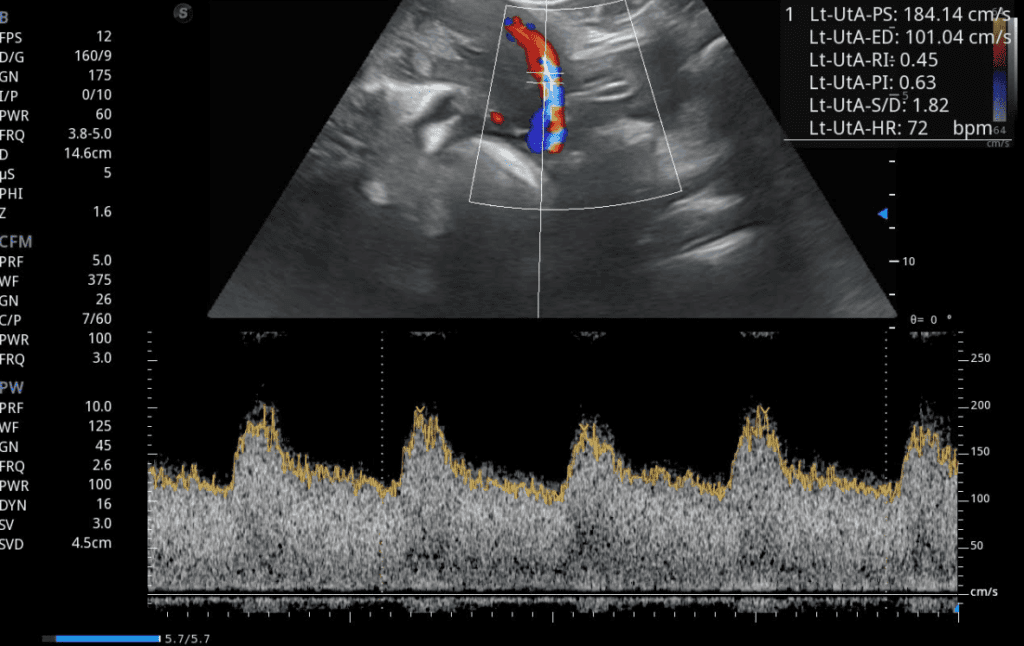

Ecografía Doppler flujo uterino embarazo

El Doppler no solo tiene valor diagnóstico, sino también predictivo y preventivo. Su uso rutinario en embarazos de riesgo ha demostrado reducir la mortalidad perinatal, mejorar la toma de decisiones médicas y optimizar los resultados del parto.

Evaluación del bienestar fetal

El Doppler permite identificar signos tempranos de sufrimiento fetal, incluso antes de que se manifiesten síntomas clínicos. Al detectar variaciones en el flujo sanguíneo, los especialistas pueden ajustar tratamientos, modificar el seguimiento prenatal o planificar un parto anticipado si es necesario.

En Preventive Health, la evaluación Doppler se integra dentro de los controles de rutina en embarazos con factores de riesgo, como antecedentes de hipertensión, diabetes, malformaciones fetales o partos prematuros previos.